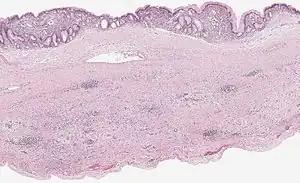

Microscopy

Mucinous cystadenoma of the pancreas